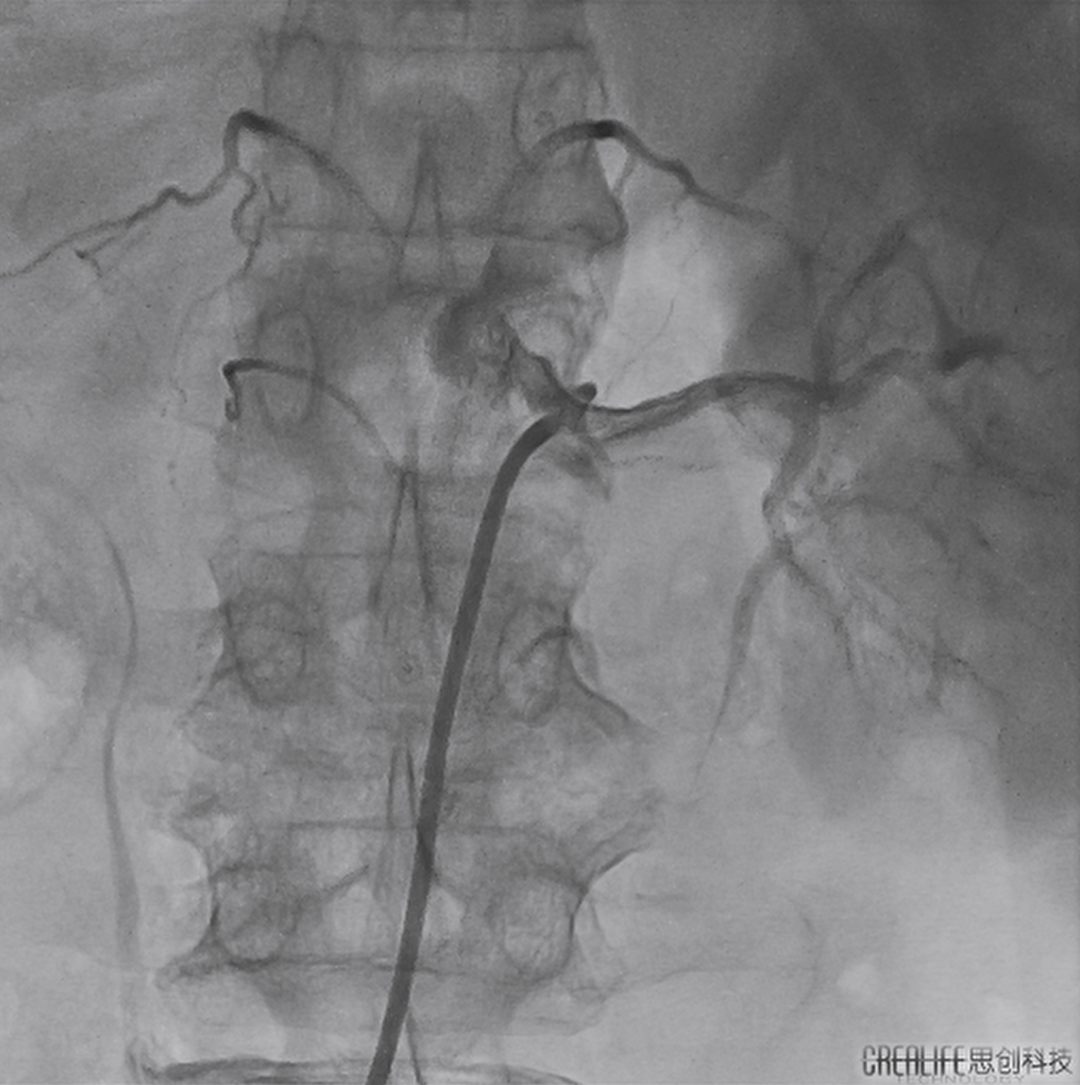

术前DSA造影

右

左

术中消融

术后造影

患者取平卧位,术前血压151/91mmHg,麻醉后行股动脉穿刺,植入8F鞘管。采用芬太尼+力月西静脉麻醉,以JR 4.0造影导管分别行左右肾动脉造影,见双侧肾动脉造影正常。随后沿导丝及造影导管送8F RDC导管送至右肾动脉开口10-15mm左右,撤回导丝以及造影导管,沿RDC导管将网篮六电极射频消融导管送入RRA远端,由远及近进行消融共6次,共计消融23个位点,消融结束无痉挛,随后8F RDC导管送至左肾动脉开口,将网篮六电极射频消融导管导管送入LRA远端,行3次消融,共计消融13个位点,消融结束造影左肾下分支轻微痉挛,给予适量硝酸甘油后缓解,复查下肢动脉穿刺无异常,予以封堵器吻合伤口,弹力绷带压迫止血。术后血压129/97mmHg。